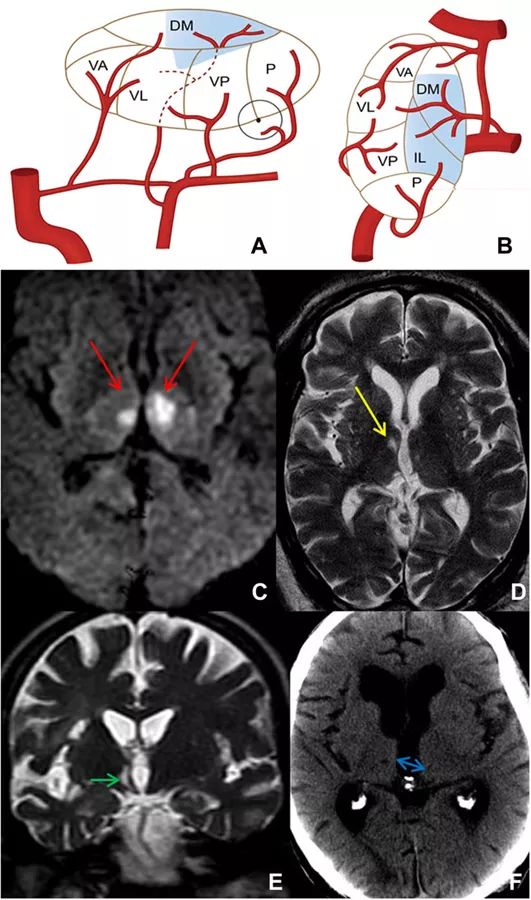

该部位由丘脑旁正中动脉供血,此动脉从PCA的P1段发出,该动脉的相关变异较多,根据不同起源部位可分为3类(图4)。

➤ I型:丘脑旁正中动脉最常见的变异,血管起源双侧对称,双侧旁正中动脉均起源于相应PCA的P1段。

➤ II型:这种变异双侧不对称,并且可分为两种亚型。IIa型双侧供血来源于同侧PCA;IIb型则是所谓的Percheron动脉,即旁正中动脉先从单侧PCA发出,随后分成两支,这个单一的动脉主干同时为双侧正中丘脑和中脑区域供血。

➤ III型:这种变异也是双侧对称的,双侧PCA发出丘脑旁正中动脉,并且两侧旁正中动脉中间有拱形血管连通。

图4 丘脑旁正中动脉的变异示意图

丘脑旁正中动脉梗死的症状取决于血管变异的类型,可能为单侧或双侧。对于单侧旁正中动脉梗死的患者,早期阶段主要表现为兴奋程度减弱和意识水平波动,可持续数小时至数天。长远上看,情绪和行为变化依然会出现,包括躁动、激越、迷失方向、冷漠等。左侧的梗死也可表现为语言功能障碍。

图5 丘脑旁正中动脉供血示意图和梗死影像学表现

Percheron动脉闭塞引起的双侧丘脑梗死已得到人们充分认识。这种综合征相对少见,占所有缺血性卒中的7%,典型的症状共包括4点:

➤ 警惕性障碍,如昏迷或木僵;

➤ 明显的记忆障碍,难以产生新的记忆,常有虚构;

➤ 本能和情绪的变化,一般伴有烦躁不安、冷漠或长期呈现不良情绪;

➤ 垂直凝视麻痹,可能没有垂直扫视和追踪动作。

其他临床症状还包括如定向力障碍、意识混乱和无动性缄默症等。大多数患者的神经系统障碍和嗜睡可恢复,但认知缺陷和冷漠症状倾向于更为严重且持久。

图6 Percheron动脉供血区梗死影像学表现